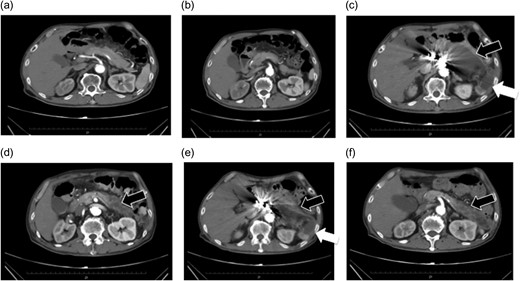

(a and b) Preoperative contrast-eCT. (c and d) eCT performed on postoperative day 13. A cyst is seen on the pancreatic tail (black arrow), while no contrast effect is seen in the spleen (white arrow). (e and f) CT performed on postoperative day 21. The pancreatic cyst has started to shrink. Part of the spleen becoming necrotic does not conflict with an etiology of ischemia due to embolization of the splenic artery.

The patient did not have preoperative risk factors for pancreatitis. Additionally, CT images taken at the arterial and late phases (180 s) did not show a contrast effect in the splenic artery distal to the embolism or the spleen. Pancreatitis occurred immediately after the arteries perfusing the pancreas were surgically embolized. Therefore, we diagnosed pancreatitis due to reduced pancreatic blood flow secondary to embolization (Fig. 2).

We confirmed the collateral pathways on preoperative CT, and imaged the SMA intraoperatively before embolizing the celiac artery, confirming communication between the branches (Fig. 2). Nevertheless, pancreatic ischemia occurred. This patient's collateral pathway through the dorsal splenic artery was considered insufficient to perfuse the pancreatic tail and spleen. Additionally, this patient had a history of endovascular aortic repair. It is possible that this previous procedure could have had adverse effects on the perfusion of the celiac artery via the SMA. If we had performed SMA arteriography at the beginning of the surgery with the celiac artery occluded by balloon, we may have been able to predict and avoid these phenomena. We should consider carefully which arteries to be embolized.